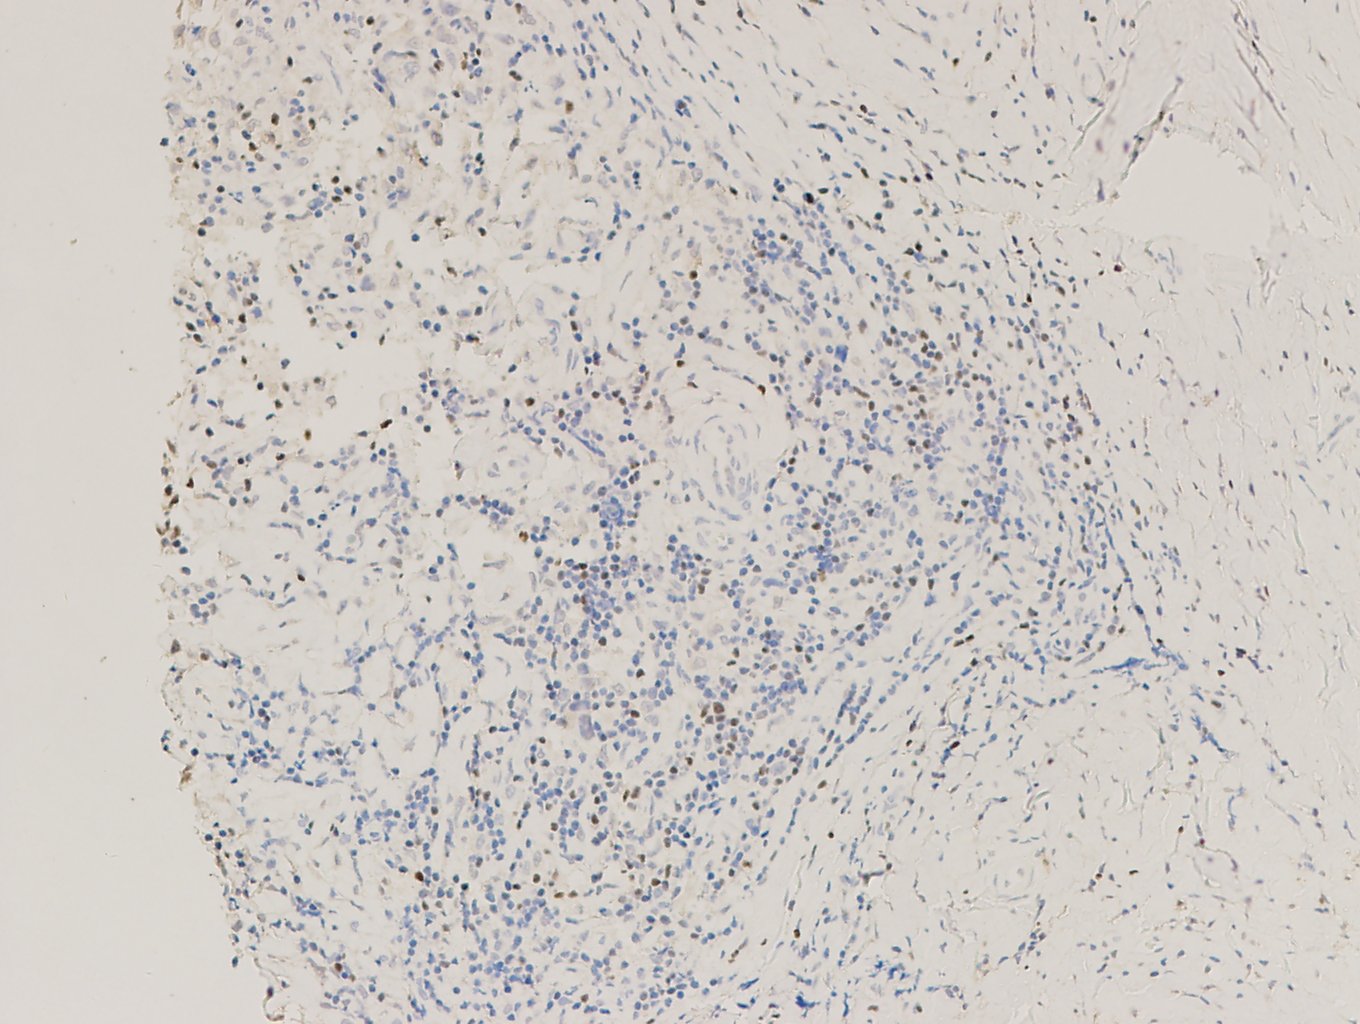

【新品单抗】FOXP3

叉头框蛋白3(FOXP3)是Forkhead转录因子家族的重要成员,研究发现其表达于多种不同组织起源的肿瘤细胞中,并且这种表达受到多种机制的调控。

| 克隆号 | 定位 | 阳性对照 | 修复条件 |

| EP340 | 细胞核 | 淋巴瘤 | 高PH热修复 |

霍奇金淋巴瘤,FOXP3染色,DAB显色